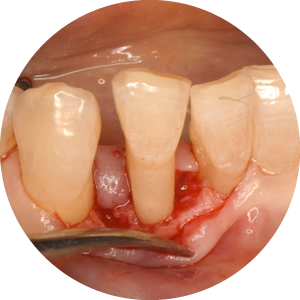

歯周外科処置

深い歯周ポケットが残っていると歯周病が進行しやすいため、歯周外科処置で歯周ポケットを浅くする手術をおすすめすることもあります。

歯周再生療法

歯周病によって失われた歯周組織を再生させる治療法です。当院ではエムドゲイン、GTR法、リグロスによる治療を行っています。

- エムドゲイン

- エムドゲインゲルを歯根の表面に塗布し、骨や歯根膜の再生を促します。保険適用外です。

- GTR法

- 歯根表面にGTR膜と呼ばれる特殊な膜を置くことで、歯槽骨、歯根膜、セメント質などの組織の再生を促します。保険適用外です。

- リグロス

- 細胞を増やす作用のあるリグロスを歯根の表面に塗布することで、歯周組織の再生が促されます。保険適用です。